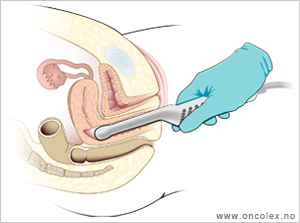

Legen kjenner på de indre organene med to fingre i skjeden og en hånd på magen.